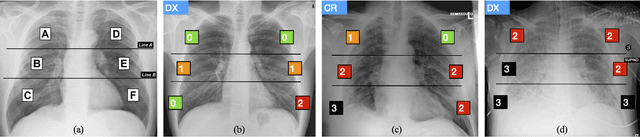

Abstract:In this work we designed an end-to-end deep learning architecture for predicting, on Chest X-rays images (CRX), a multi-regional score conveying the degree of lung compromise in COVID-19 patients. Such semiquantitative scoring system, namely Brixia-score, was applied in serial monitoring of such patients, showing significant prognostic value, in one of the hospitals that experienced one of the highest pandemic peaks in Italy. To solve such a challenging visual task, we adopt a weakly supervised learning strategy structured to handle different tasks (segmentation, spatial alignment, and score estimation) trained with a "from part to whole" procedure involving different datasets. In particular, we exploited a clinical dataset of almost 5,000 CXR annotated images collected in the same hospital. Our BS-Net demonstrated self-attentive behavior and a high degree of accuracy in all processing stages. Through inter-rater agreement tests and a gold standard comparison, we were able to show that our solution outperforms single human annotators in rating accuracy and consistency, thus supporting the possibility of using this tool in contexts of computer-assisted monitoring. Highly resolved (super-pixel level) explainability maps were also generated, with an original technique, to visually help the understanding of the network activity on the lung areas. We eventually tested the performance robustness of our model on a variegated public COVID-19 dataset, for which we also provide Brixia-score annotations, observing good direct generalization and fine-tuning capabilities that favorably highlight the portability of BS-Net in other clinical settings.